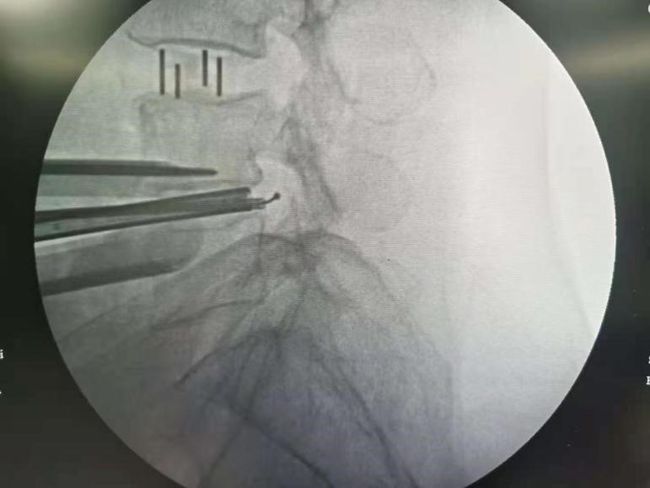

手术团队充分讨论,患者诊断明确,需手术解除椎管狭窄及恢复腰椎稳定。传统开放手术可以解决问题,但创伤较大,出血会较多,同时患者身体较差,存在一定风险。与患者沟通后,邵女士希望能微创手术治疗,最后决定行微创OLIF+内镜手术

进一步完善术前检查后,余将明副主任医师亲自主刀,手术2小时左右,手术顺利,术后疼痛消失,患者恢复良好,非常满意。

本病例患者L3/4存在腰椎滑脱、椎间隙高度丢失;但L4/5椎间隙高度丢失不明显,所以选择了L3/4、L4/5两个节段的OLIF同是进行L4/5的内镜手术(OLIF+内镜),充分的结合了两种术式的优缺点,是间接减压与直接减压的完美结合。所以对于严重的椎管狭窄或滑脱也是可以采用微创的方式来解决的。目前国内开展此类微创手术鲜有报道。